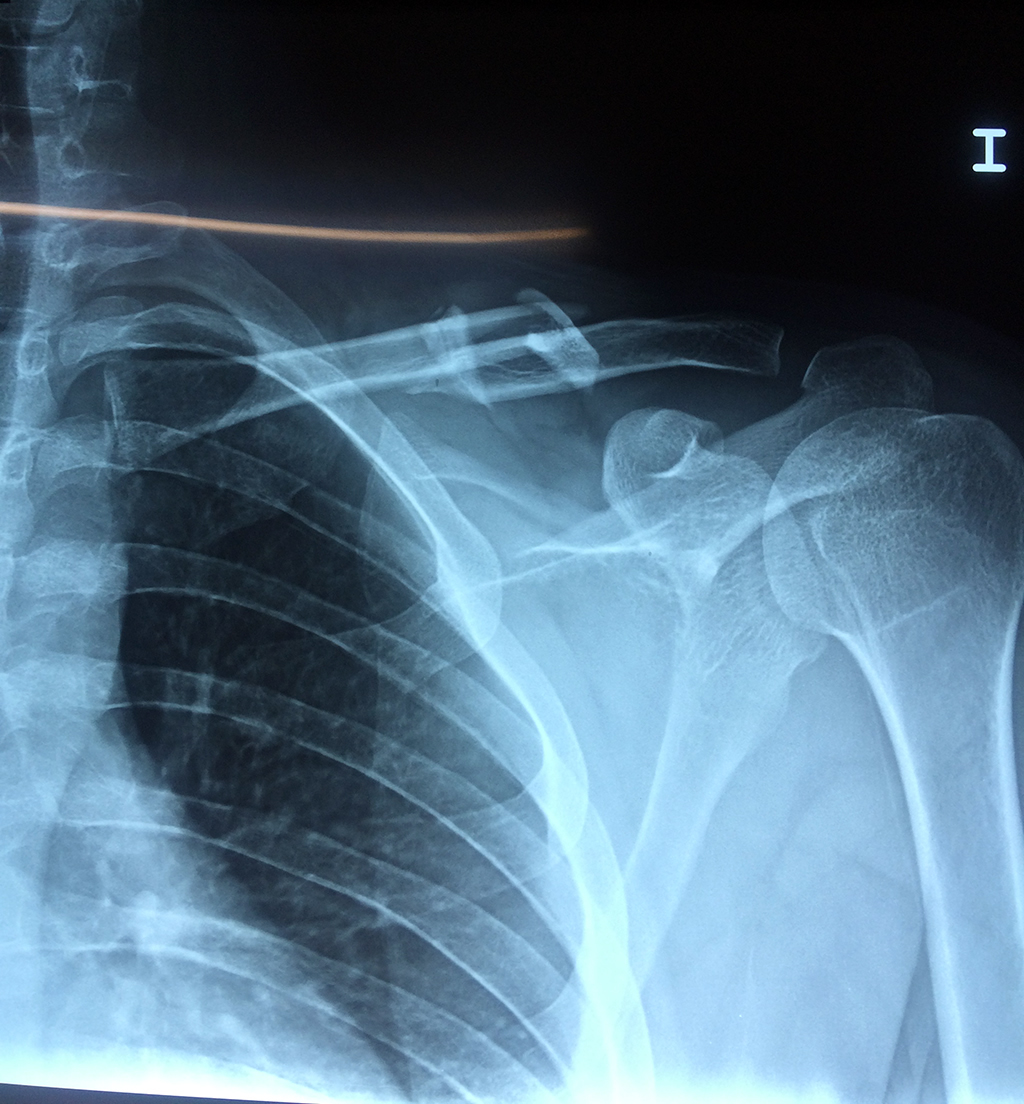

La clavícula es un hueso largo, con forma de "S" itálica, situado en la parte anterosuperior del tórax. Junto con la escápula forman la cintura escapular. Se puede palpar por toda su longitud y se extiende del esternón al acromion de la escápula, siguiendo una dirección oblicua lateral y posterior.

Se considera el único medio de unión entre el miembro superior y el tórax. A pesar de su aspecto, similar al de un hueso largo, posee una estructura semejante a la de un hueso plano, ya que carece de epífisis y de diáfisis, lo que la harían entrar dentro de la clasificación de hueso largo. Carece de un canal medular propiamente dicho.